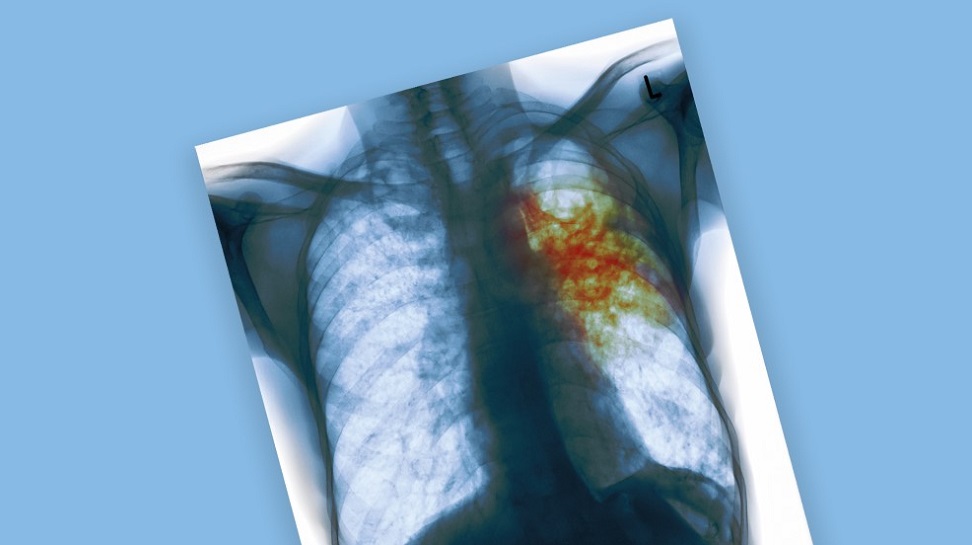

Всемирный день борьбы с туберкулёзом

Туберкулёз – инфекционная болезнь, которую вызывают микобактерии туберкулёза. Наиболее часто при туберкулёзе поражаются лёгкие. Иногда туберкулёз называют социальной болезнью, поскольку она часто встречается у людей с низким уровнем жизни, испытывающих стресс и лишения в повседневной жизни. Однако, несмотря на правильность этого тезиса, заболеть туберкулёзом может абсолютно каждый – ведь все мы контактируем с внешним миром, а микобактерии все равно, где жить.

Туберкулёз

Туберкулёз – широко распространенное инфекционное заболевание, вызываемое микобактериями. Возбудитель туберкулёза – бактерия Mycobacterium tuberculosis. Она устойчива во внешней среде и в некоторых случаях способна сохраняться в высушенном виде годами. Источник инфекции – больные активной формой туберкулёза люди.